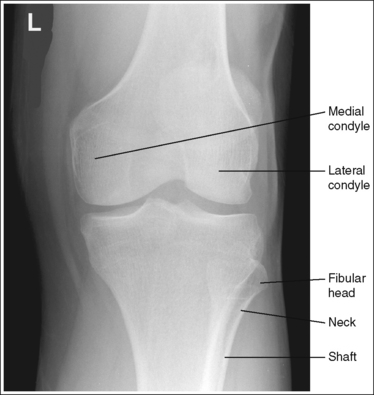

The knee demonstrates an AP projection. The medial and lateral femoral epicondyles are in profile, the femoral condyles are symmetrical, the intercondylar eminence is centered within the intercondylar fossa, and the tibia is superimposed over 0.25 inch (0.6 cm) of the fibular head.

• To obtain an AP knee projection, place the patient in a supine position with the knee fully extended. Internally rotate the leg until an imaginary line drawn between the medial and lateral femoral epicondyles is positioned parallel with the IR (Figure 6-71). This positioning places the medial and lateral femoral epicondyles at equal distances from the IR as well as medially and laterally in profile, respectively. It also centers the intercondylar eminence within the intercondylar fossa and draws the fibular neck and a portion of the fibular head from beneath the tibia.

• Effect of rotation. If the femoral epicondyles are not positioned parallel with the IR, an AP projection has not been obtained. If the patient's leg was not internally rotated enough to place the epicondyles at equal distances from the IR, they are not in profile, the medial femoral condyle appears larger than the lateral condyle, and the tibia is superimposed over more than 0.25 inch (0.6 cm) of the fibular head (see Image 54). If the patient's leg was internally rotated more than needed to place the femoral epicondyles at equal distances from the IR, the epicondyles are not demonstrated in profile, the lateral femoral condyle appears larger than the medial condyle, and the tibia is superimposed over less than 0.25 inch (0.6 cm) of the fibular head (see Image 55).

The knee joint space is open, the anterior and posterior condylar margins of the tibia are superimposed, the intercondylar eminence and tubercles are demonstrated in profile, and the fibular head is demonstrated approximately 0.5 inch (1.25 cm) distal to the tibial plateau.

• The anterior and posterior condylar margins of the tibia are superimposed if the correct central ray angulation, as determined by the patient's upper thigh and buttocks thickness, is used. By studying the tibial plateau region, you will see that the tibial plateau slopes distally approximately 5 degrees from the anterior condylar margin to the posterior condylar margin on both the medial and lateral aspects (Figure 6-72). Only if the central ray is aligned parallel with the tibial plateau slope is an open knee joint space obtained.

• Determining the central ray angulation. When a patient is placed in a supine position, the degree and direction of the central ray angulation required depend on the thickness of the patient's upper thigh and buttocks. This thickness determines how the lower leg and the tibial plateau align with the IR. Figure 6-73 shows a guideline that can be used to determine the central ray angulation for different body sizes; it illustrates the relationship of the tibial plateau to the imaging table as the patient's upper thigh thickness increases. Note that a decrease occurs in femoral decline, and a shift occurs in the direction of the tibial plateau slope as the thickness of the thigh decreases. Because of this plateau shift, the central ray angulation must also be adjusted to keep it parallel with the plateau and to achieve an open knee joint. For optimal AP knee projections, measure from the patient's anterior superior iliac spine (ASIS) to the imaging table on either side to determine the central ray angulation to use for each knee examination. When measuring this distance, do not include the patient's abdominal tissue. Keep the calipers situated laterally next to the ASIS. If the measurement is less than 18 cm, a 5-degree caudal angle should be used. If the measurement is 19 to 24 cm, a perpendicular beam should be used. If the measurement is greater than 24 cm, a 5-degree cephalad angle should be used. Using the correct central ray angulation not only results in an open knee joint space but also provides optimal demonstration of the intercondylar eminence and tubercles without foreshortening.

• Analysis of joint space narrowing. On an AP knee projection with adequate positioning, joint space narrowing is evaluated by measuring the medial and lateral aspects of the knee joint, which are also referred to as compartments. The measurement of each of these compartments is obtained by determining the distance between the most distal femoral condylar surface and the posterior condylar margin of the tibia on each side. Comparison of these measurements with each other, with measurements from previous images, or with measurements of the other knee determines joint space narrowing or a valgus or varus deformity. In a valgus deformity the lateral compartment is narrower than the medial compartment; in a varus deformity the medial compartment is narrower (see Images 56 and 57). Precise measurements of the compartments are necessary to ensure early detection of joint space narrowing and are best obtained when the knee joint space is completely open. If an inaccurate central ray angulation was used for an AP knee projection, the knee joint is narrowed or obscured, the intercondylar eminence and tubercles are foreshortened, and the tibial plateau is demonstrated.